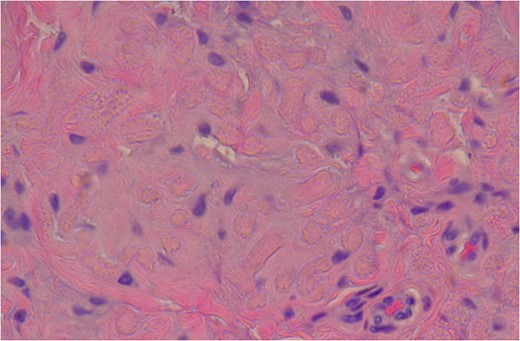

Mason’s Trichome stain outlining collagen around the abnormal elastic fibres with the characteristic serrated edges or petalloid globules. It outlines the elastic fibres by negative staining.

Histological sections show an admixture of alternating collagen bundles with abnormal elastic fibres. The elastic fibres have a degenerate fragmented appearance of petalloid globules or chenille bodies. The Verhoeff stain confirms these abnormal elastic fibres [9] (Fig. 9).

The Mason’s Trichrome stain also confirmed the diagnosis by identifying the elastic fibres by negative staining. The elastic fibres appear brown on the histological slides [9] (Fig. 10). MRI remains the diagnostic imaging modality of choice. It has the added advantage of detecting contralateral subclinical lesions which would clinch the diagnosis as in this case. A second issue is the left sided tumour which was not excised at the original surgery. The patient continues to remain asymptomatic on the left side and the tumour remains clinically impalpable. The patient has opted for conservative management of this lesion in the interim. There has been no increase in size to date and we have decided on serial imaging unless the patient becomes symptomatic.